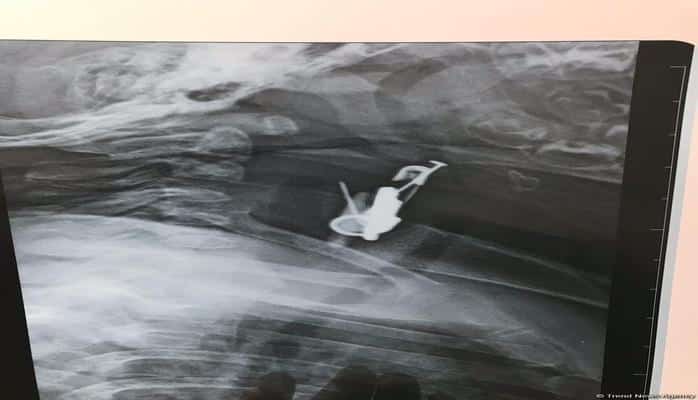

Azərbaycanda altı aylıq körpənin mədəsindən sancaq və digər cisimlər çıxarılıb.

Valideyn tərəfindən Bakıya xəstəxanaya çatdırılan uşağın mədəsində yad cismin olduğu məlum olub. Belə ki, altı aylıq körpə sancağı və üzərində olan digər əşyaları udub. Ə.F.Qarayev adına 2 saylı uşaq kliniki xəstəxanasında endoskopik üsul ilə körpənin mədəsindən həmin əşyalar çıxarılıb.